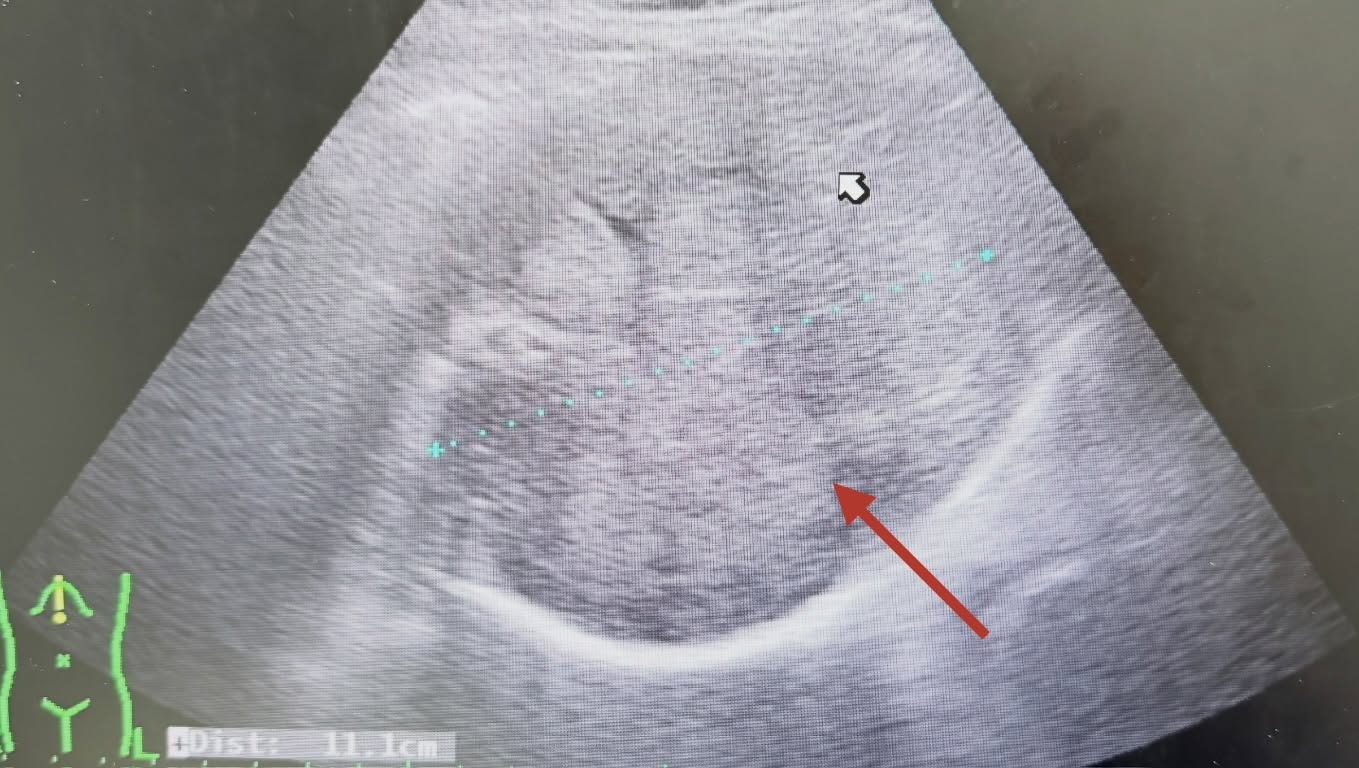

胃腸肝膽科醫師張靖在社群平台分享案例指出,許多人誤以為腫瘤只要透過手術切除就算治療完成,實際上若忽略後續追蹤,仍可能出現復發或惡化的情況。這名患者因上腹部感到不適而前來就診,透過腹部超音波檢查時,醫師發現肝臟內出現大量腫瘤。進一步了解才知道,他過去曾動過肝腫瘤手術,但術後多年未再定期檢查,才導致病情發展到相當嚴重的程度。